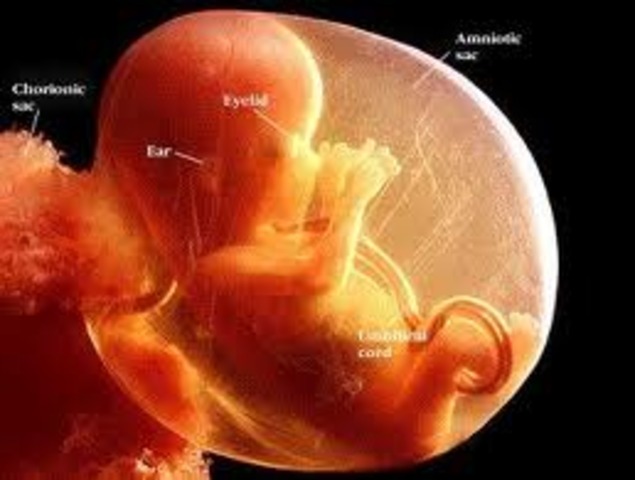

• Week 17

Week 17

Your baby now weighs in at a whopping three to five ounces, and he's four to five inches in length. The bones that are now in place in his ears means he can probably hear your voice as you talk to your partner and pals and sing in the car. While he’s getting used to your voice, the tiny muscles in his body, especially the ones in his back, are gaining strength, so he can straighten out a little more.